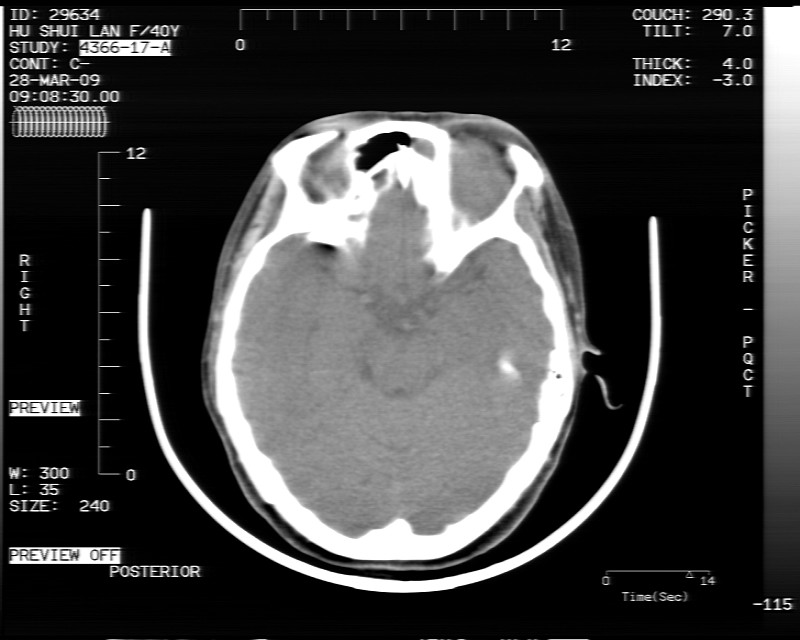

女性,40岁,左眼疼痛,视力模糊,五年曾行左眼脂肪瘤手术。

患者现病史不知持续有多久了,现片示眶内病灶边缘较模糊,眶脂混浊,多考虑炎性假瘤,不除外肿瘤

1)左眼眶内占位性病变,性质待定(不排除炎性假瘤);建议行进一步检查。2)左侧额窦炎。